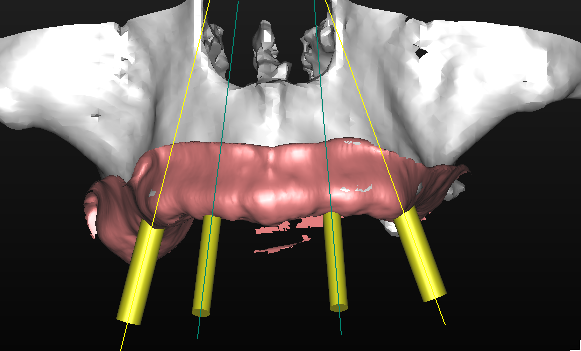

La pianificazione con Simplant permette l’accoppiamento tra la protesi e i tessuti molli oltre alla corretta valutazione della posizione, dell’inclinazione e dell’orientamento tridimensionale degli impianti (Figg. 15-17). Questo tipo di progettazione consente di eseguire una procedura chirurgica protesicamente guidata, sfruttando l’emergenza degli impianti nella loro più ideale posizione, con benefici dal punto di vista protesico e biomeccanico (Figg. 18, 19)

Grazie a questo tipo di pianificazione il software produce una guida chirurgica che viene stampata da una stampante 3D e consente al chirurgo di operare con tecnica “flapless” cioè senza la necessità di aprire dei lembi e causare un maggiore traumatismo al paziente. La guida chirurgica trasparente viene provata in bocca al paziente prima dell’intervento chirurgico per testare la sua stabilità e precisione nel rapporto con i tessuti molli (Figg. 20, 21). In questo caso specifico si era pianificato di utilizzare un nuovo approccio con degli impianti e componenti protesiche particolari, la tecnica “Smart fix” di Astra Tech Implant (Dentsply Sirona) (Figg. 22-25).

I due impianti più posteriori (Astra Tech Implant System EV, Densply Sirona) hanno un design particolare, sono disegnati con un profilo diverso dal normale, con un collare anziché piatto inclinato in maniera tale da consentirne il posizionamento con un asse ed un’angolazione antero posteriore, adattandosi così nella loro emergenza alla cresta ossea (Fig. 22). I due impianti anteriori soni impianti standard, in questo caso con diametro 3,5 mm (Fig. 23). La componentistica protesica prevede MUA (multi unit abutments, multibase Dentsply Sirona) standard sui due impianti anteriori (Fig. 24) e due MUA angolati componibili ed orientabili sui due impianti posteriori (Fig. 25).